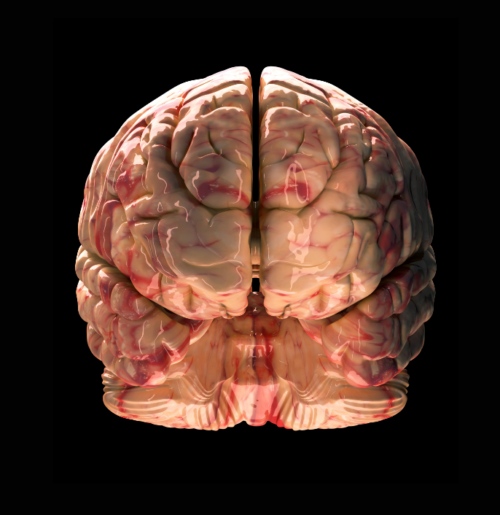

FITC-Dextran and TRITC-Dextran: Essential Tools for Blood-Brain Barrier Research